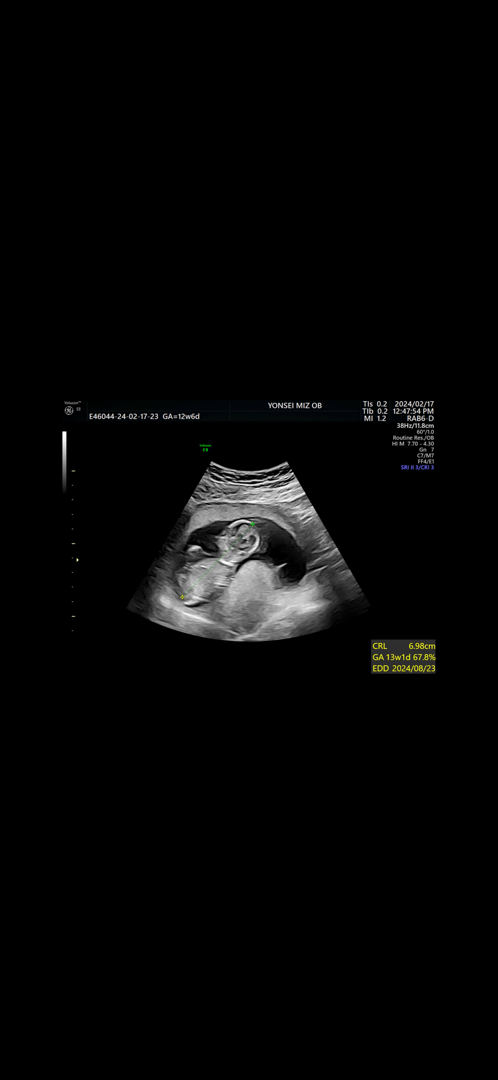

12주 6일) 각도법 고수님들의 도움이 필요합니다ㅠㅠ

저희 아가도 띠용인데! 이 사진은 각도법 못보지않나요~?